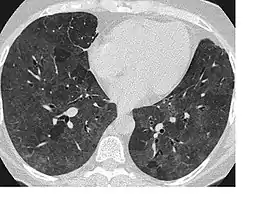

Симптом «матового стекла»

Симпто́м «ма́тового стекла́» — неспецифический радиологический симптом, отражающий различные патологические изменения в лёгочной ткани на уровне альвеол. Визуализируется при компьютерной томографии как туманное, матовое снижение прозрачности лёгочной ткани с дифференцируемым рисунком сосудов и бронхов на этом фоне. Данный симптом может быть обусловлен частичным снижением воздушности лёгочных альвеол (транссудативной, экссудативной или иной природы), их частичным спадением (гиповентиляцией) или утолщением их стенок. Так как данный симптом неспецифичен, необходимо иметь в виду анамнестические данные, клиническую картину и сопутствующую патологию. В связи с известной субъективностью оценки наличия симптома «матового стекла», следует учитывать параметры сканирования и визуализации; так, слишком узкое лёгочное окно создаёт «пятнистость» изображения, искажающую истинную картину, а низкое разрешение и большая толщина срезов (более 4 мм) создают эффект усреднения, скрадывающий и размывающий мелкие детали.

Пациент с экзогенным аллергическим альвеолитом. Обширные зоны снижения воздушности лёгочной ткани по типу «матового стекла», на фоне которых определяются «воздушные ловушки». | |

| Вид исследования | компьютерная томография |

| Область исследования | грудная клетка |